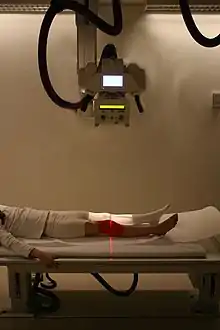

This fracture of the lower cervical vertebrae is one of the conditions treated by orthopedic surgeons and neurosurgeons. | |

Orthopedic surgery or orthopedics (alternatively spelt orthopaedics) is the branch of surgery concerned with conditions involving the musculoskeletal system.[1] Orthopedic surgeons use both surgical and nonsurgical means to treat musculoskeletal trauma, spine diseases, sports injuries, degenerative diseases, infections, tumors, and congenital disorders.